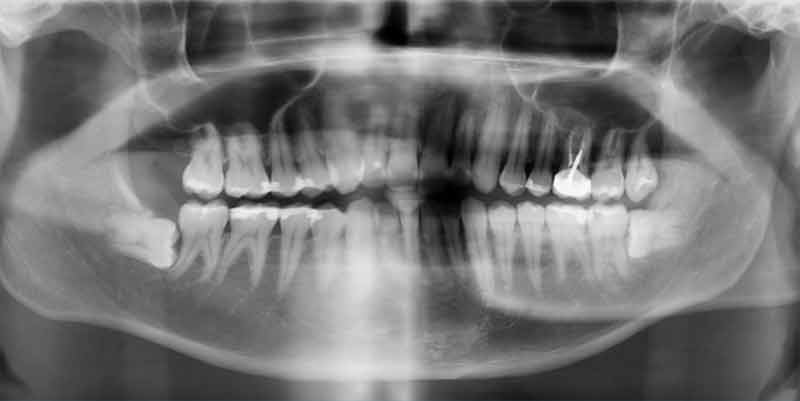

水平智齒/阻生齒

智齒大約在17~21歲左右就會開始生長,有時候智齒沒辦法順利的從牙齦冒出來,這常是因為空間不夠讓它長出來,或是它長錯方向了,而這些長不出來的智齒,我們稱它為阻生智齒及水平智齒。

完全沒有長出的智齒有可能引起囊腫,雖然是良性的,但會因為物理傷害鑿空骨頭,引起下巴骨折;或因壓迫神經造成神經麻痺,需治醫院開刀。